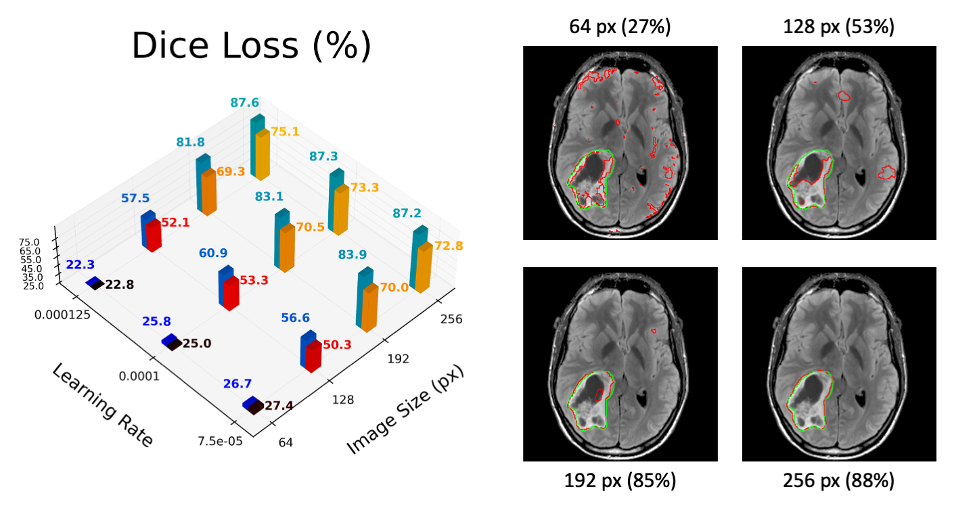

Using Covalent, we tested the improved workflow on the same twelve hyperparameter combinations (four different image sizes and three different learning rates). The results after twenty epochs are visualized below. In the 3D chart, we report the Sørensen-Dice coefficient between the model’s prediction and the correct segmentation area. This metric approaches 100% if and only if the predicted and true masks have the exact same shape and orientation. Four representative output images are also shown on the right-hand side of the figure below. While admittedly small, the experiment suggests that (1) the optimal learning rate is around 0.0001 and (2) that performance degrades significantly if the input images are reduced to a size below about 192 by 192 pixels.

Figure 5 – Mean (black/red/yellow) and median (blue/teal) dice loss with typical results at each image size.

If the experimenter desires better predictions, they can immediately redeploy the workflow at any scale by dispatching the lattice with a new list of parameters. Further along, a new strategy can be implemented by editing hp_sweep(); for example, to incorporate any post-processing or to accept value ranges instead of an explicit parameter list. With Covalent, it’s always easy to undo these changes and we can always revisit older workflows in the Covalent UI.